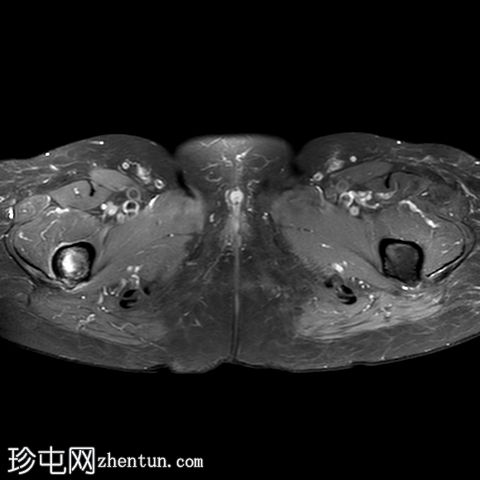

X光片

右股骨干近端1/3可见外侧皮质轻微骨膜增厚。内侧皮质正常。除关节周围软组织钙化外,髋关节未见异常。